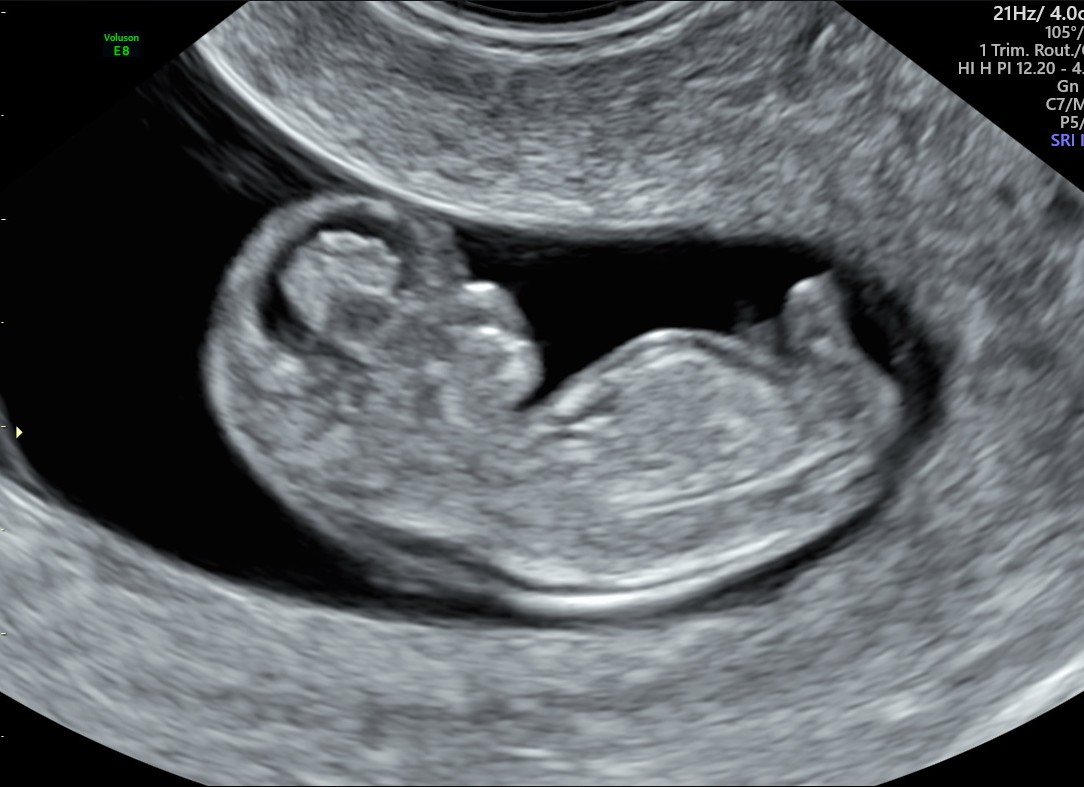

Well-being/Reassurance scan 12 -20 wks

£85